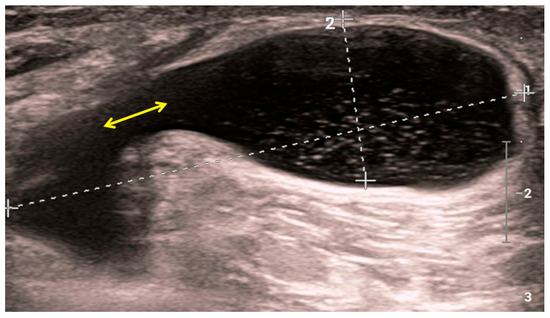

4. Radiological Characteristics of Osteoarthritis